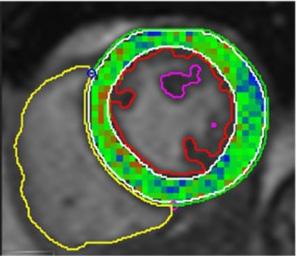

L’acquisition de cette manœuvre respiratoire et les analyses génèrent une cartographie de l’oxygénation myocardique. Rappelons que ces résultats sont dérivés d’une méthode qui n’a pris que quelques minutes à exécuter. La figure 4 présente quelques exemples des cartes obtenues.

Figure 4 : L’intensité du signal démontrant la réserve d’oxygénation du myocarde. A- Oxygénation myocardique globale chez un volontaire sain avec une augmentation globale et homogène de l’intensité du signal; B- Anomalie régionale (diminution de l’oxygénation du myocarde) chez un patient présentant une sténose coronarienne sévère; C- Réduction globale de l’oxygénation myocardique chez un patient qui souffre d’insuffisance cardiaque. La barre de couleur (à droite) fournit une légende pour les différences d’intensité du signal qui correspondent aux différences d’oxygénation myocardique. Les changements négatifs de l’intensité du signal sont mis en évidence par le bleu et le noir, ce qui représente une réponse d’oxygénation altérée, tandis que les changements positifs de l’intensité du signal sont mis en évidence par le vert, ce qui représente une réponse d’oxygénation saine.